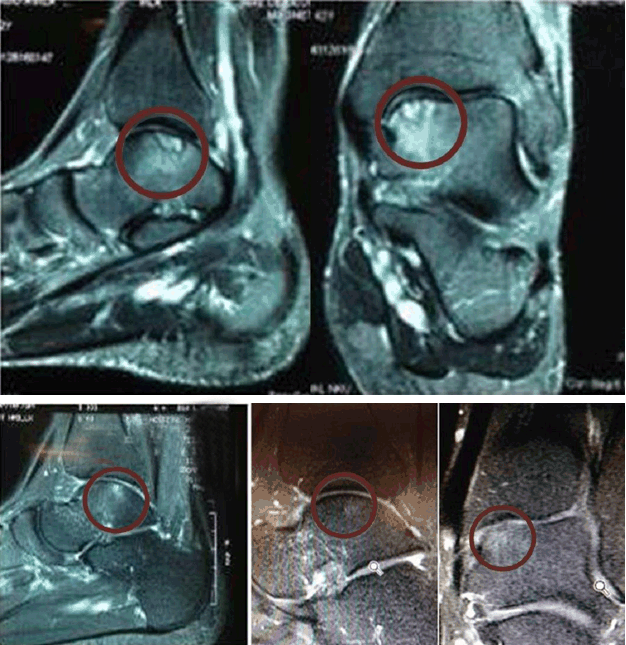

A 30-year-old male civil engineer, and a professional yachting (soling class) athlete. He sought medical attention reporting pain on the right knee following a game of padel tennis and sailing. He also complained of discomfort while walking and ascending/descending stairs. Physical examination showed neutral alignment of lower limbs, pain and crepitation during mobilization of the femoropatellar joint. Ligament and meniscal tests were normal. Flexion motion ranges were 130° on the right knee and 145° on the left one. Extension was complete bilaterally. Patient’s body measurements were 1.81 m, 80 kg and BMI of 24.69 kg/m2. An MRI scan of the right knee performed on the same day of his medical consultation showed patellar chondropathy with chondral fissures in the apex and medial facet, reaching into the deeper layers (Figure 3A). The images demonstrated stress areas on the subchondral structures of the facets and the patellar ridge. Final diagnosis was knee pain due to patellar chondropathy. Treatment included daily oral intake of 10 g collagen hydrolysate (Fortigel®), physiotherapy and interruption of high-impact activities (such as sailing). On his return one month later the patient reported improvement of symptoms and decrease in the right knee pain. This patient presented a clinical and radiological picture indicative of osteochondral pathology at the level of the left ankle and a sequela of sprain with joint trauma, which caused him to withdraw from soccer practice and from races. He presented limitation of the joint mobility of the affected ankle, which recovered after interdisciplinary treatment and use of bioactive collagen peptide. With the functional recovery obtained clinically and radiologically, he was able to return to the partial progressive practice of his sports activities, with orientation to maintain the prescribed therapeutic measures. He was counseled to maintain the intake of collagen hydrolysate and re-initiate his training program since he would participate on an International Yachting Event (Soling Class) in one month. On his next consultation, after two months, the patient reported being asymptomatic and pain-free and also that he had been classified among the first six finalists on the yachting event. Physical examination showed normal mobility range on both knees, with 145° flexion and complete bilateral extension. A new MRI scan, performed on the same period, revealed signs of patellar chondropathy on the apex and medial facet, reaching only the superficial layers (Figure 3B). The exam showed reduction of the OCL on the facets and patellar ridge, in comparison to the previous one. The patient was advised to continue the use of the collagen hydrolysate Fortigel®, maintain his anaerobic activities (such as weight lifting) and also the aerobic training. The clinical and radiologic functional recovery allowed the patient to keep his sports activities and he became champion of the local boat race (XXI Copa da Cidade de Porto Alegre) in March 2015.

Figure 3: (A) Note the patellar chondropathy with chondral fissures in the apex and medial facet, reaching into the deeper layers (MRI 10/01/2014), (B) Note reduction of the OCL on the apex and medial facets and patellar ridge, reaching the superficial layers (MRI 01/16/2015).